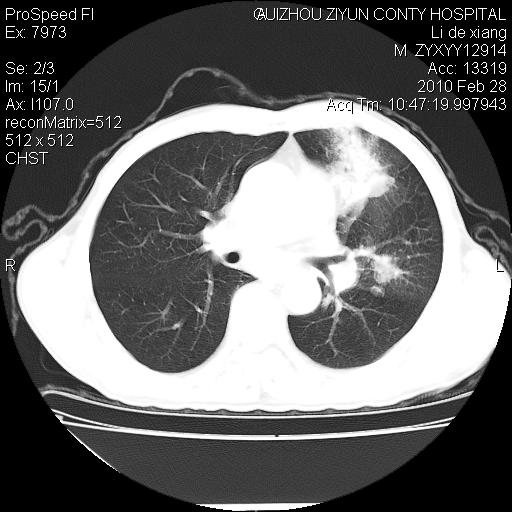

标题: CT24776:男 71Y 咳嗽咳痰胸痛两月,伴声音嘶哑。 [打印本页]

左侧中央型肺癌伴左肺上叶阻塞性肺炎及节段性不张可能性大,建议纤支镜检查!

左侧中央型肺癌伴左肺上叶阻塞性肺炎及节段性不张可能性大,建议纤支镜检查!纵隔淋巴结转移.

左肺门部肿块,伴左上肺斑块影,周边模糊,支持左肺中央型肺癌伴节段性不张及阻塞性肺炎,结合支气管镜检查。

左上叶支气管狭窄,阻塞性病变,肺门肿块,纵隔及肺门淋巴结增大,中央性肺癌